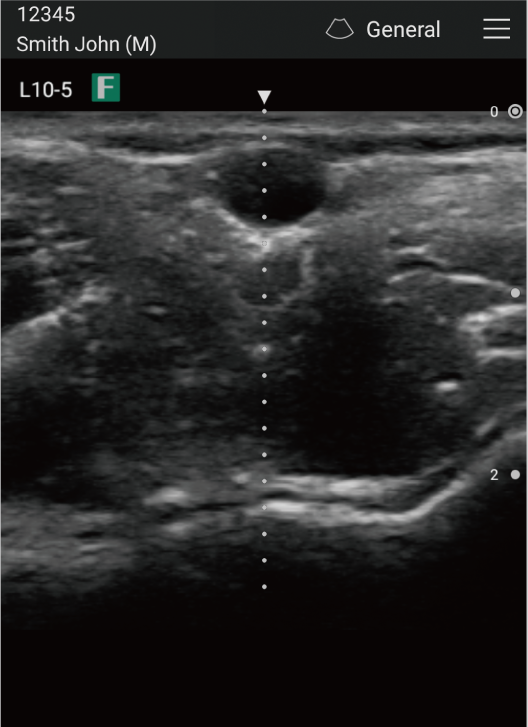

Carotid artery long axis view

Center Line

Brachial artery center line display possible

Blood flow evaluation is enabled by the Color-Mode Scan. With centerline display, it also supports puncture procedures.